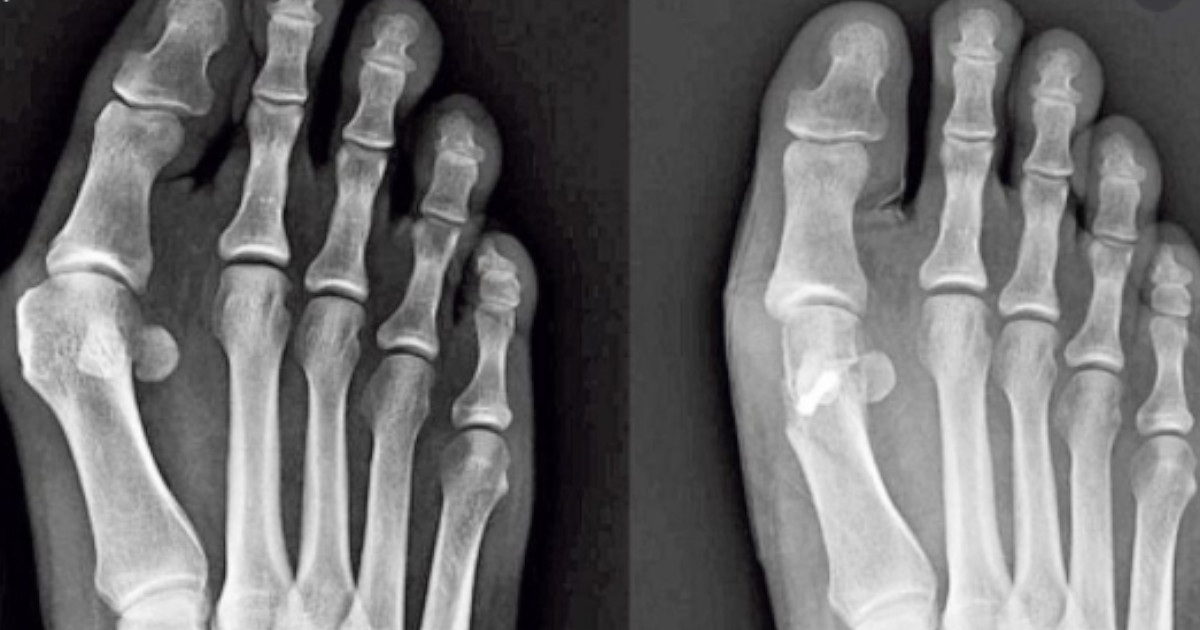

Haluks to wybrzuszenie, które wydaje się zaczerwienione lub spuchnięte u podstawy dużego palca u nogi. Gdy zgrubienie się pogłębia, paliczki u podstawy dużego palca mogą wystawać dalej. Objawy halluksów mogą być różne.

Wszystkie objawy haluksów są podobne. Można zaobserwować wybrzuszenie przy dużym palcu u nogi, zaczerwienienie, obrzęk i bolesność w miejscu haluksa. Wybrzuszenie może powodować, że osoba odczuwa drętwienie i mrowienie, a także zwiększony nacisk na palce.